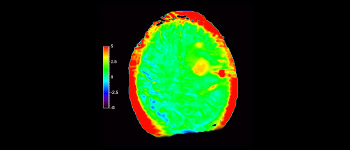

Dans une société où les troubles neurologiques sont importants, Philips s’engage à fournir une qualité de diagnostic irréprochable et la meilleure orientation thérapeutique pour tous les patients. De nos jours, même si l’IRM est une référence en imagerie neuro-oncologique, sa précision en termes de classement des tumeurs et l’évaluation du suivi du traitement peuvent être davantage améliorées. 3D APT (Transfert de proton amide) est une nouvelle méthode d’IRM cérébrale unique et sans contraste qui répond au besoin de fiabilité pour les diagnostics neuro-oncologiques. 3D APT utilise la présence de protéines cellulaires endogènes pour produire un signal RM qui est directement lié à la prolifération cellulaire, indicateur de l’activité tumorale. 3D APT peut aider les professionnels de santé formés à différencier les gliomes cérébraux de haut grade par rapport aux gliomes cérébraux de bas grade, ainsi que l’évolution de la tumeur par rapport aux effets du traitement1.

avec 3D APT